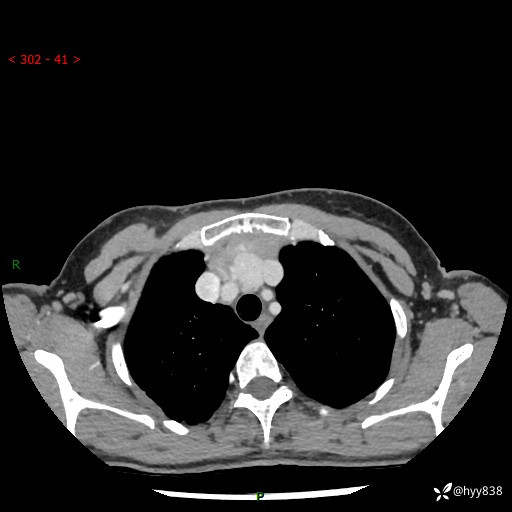

增强动脉期+静脉期